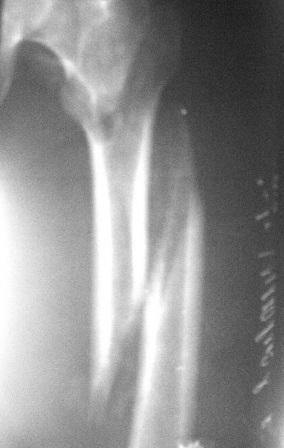

Больному 50л. В отдаленном от центра р-не ДТП 6.12.08г. д-з " тяжелая ЧМТ, мн.перломы ребер слева,отрыв ножки селезенки, повреждение п/ж железы, з/двойной перелом прав.бедра.

После экстрен. хирургических вмешательств, конечность фиксирована кокситной гипсовой лонгетной повязкой. Кома 2 нед, нагноение п/о раны живота, посттравмат. пневмония. 20.01.09г. переведен к нам. Постельный больной, ослабленный,бледный, весом 56кг: свищ п/о раны перед. брюшной стенки с сукровичным выделением, гипс снят - деформация и укорочение бедра на 6 см, в обл перелома есть спайка. слабо, но активно поднимает ногу, контрактура т/б и коленных суставов. Обшеукреп. лечение, компоненты крови, общ. массаж, ЛФК и больной активизирован, начал ходить с костылями, движения в суставах почти восстановлены. НВ-112, эр-3,5млн. Наш план блокир. и/м остеосинтез. Имеется гвозди для ВНПБ ЦИТО, но PFN не имеется

Тут нужен не тот или другой вариант интраоперационного дистрактора, который работает при хорошей еще подвижности отломков, т.е в ближайшие недели после перелома. В срок 6 недель после травмы одномоментную репозицию с удлинением на 6 см делать не надо даже пытаться, это травматично. Лучше наложить нормальный дистракционный аппарат.

Вертельный перелом уже срастается в приемлемом положении отломков. Для сохранения шеечно-диафизарного угла в проксимальной опоре аппарата по оси шейки можно ввести 2-3 стержня.

Лучше сделать остеоклазию на уровне диафиза секциями аппарата (ротацией), затем проводить дистракцию темпом 2-4 мм/сут дробно, в пределах переносимости пациентом. После восстановления длины и сопоставления диафиза по оси закрыто заштифтовать. Имеющийся стержень вполне подойдет, поскольку вертельный перелом уже не будет требовать остеосинтеза.